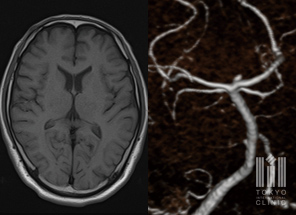

頭部MRI/MRA検査

あらゆる角度から脳の健康状態を確認。特に、頭部MRI・頭頚部MRA検査を併用することで、 脳の異常の早期発見に努めます